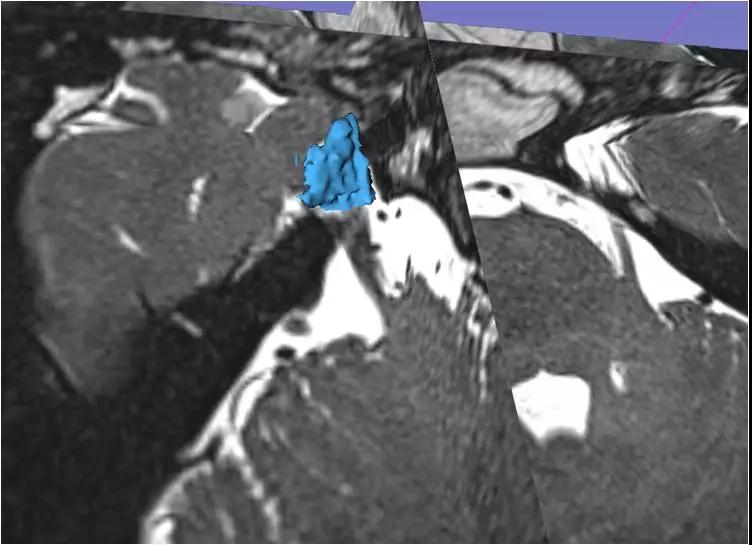

(术前根据卵圆孔大小及形态精确设计穿刺针道)

(术前利用3D-slicer软件精确重建右侧Meckel’s腔并计算其容积)